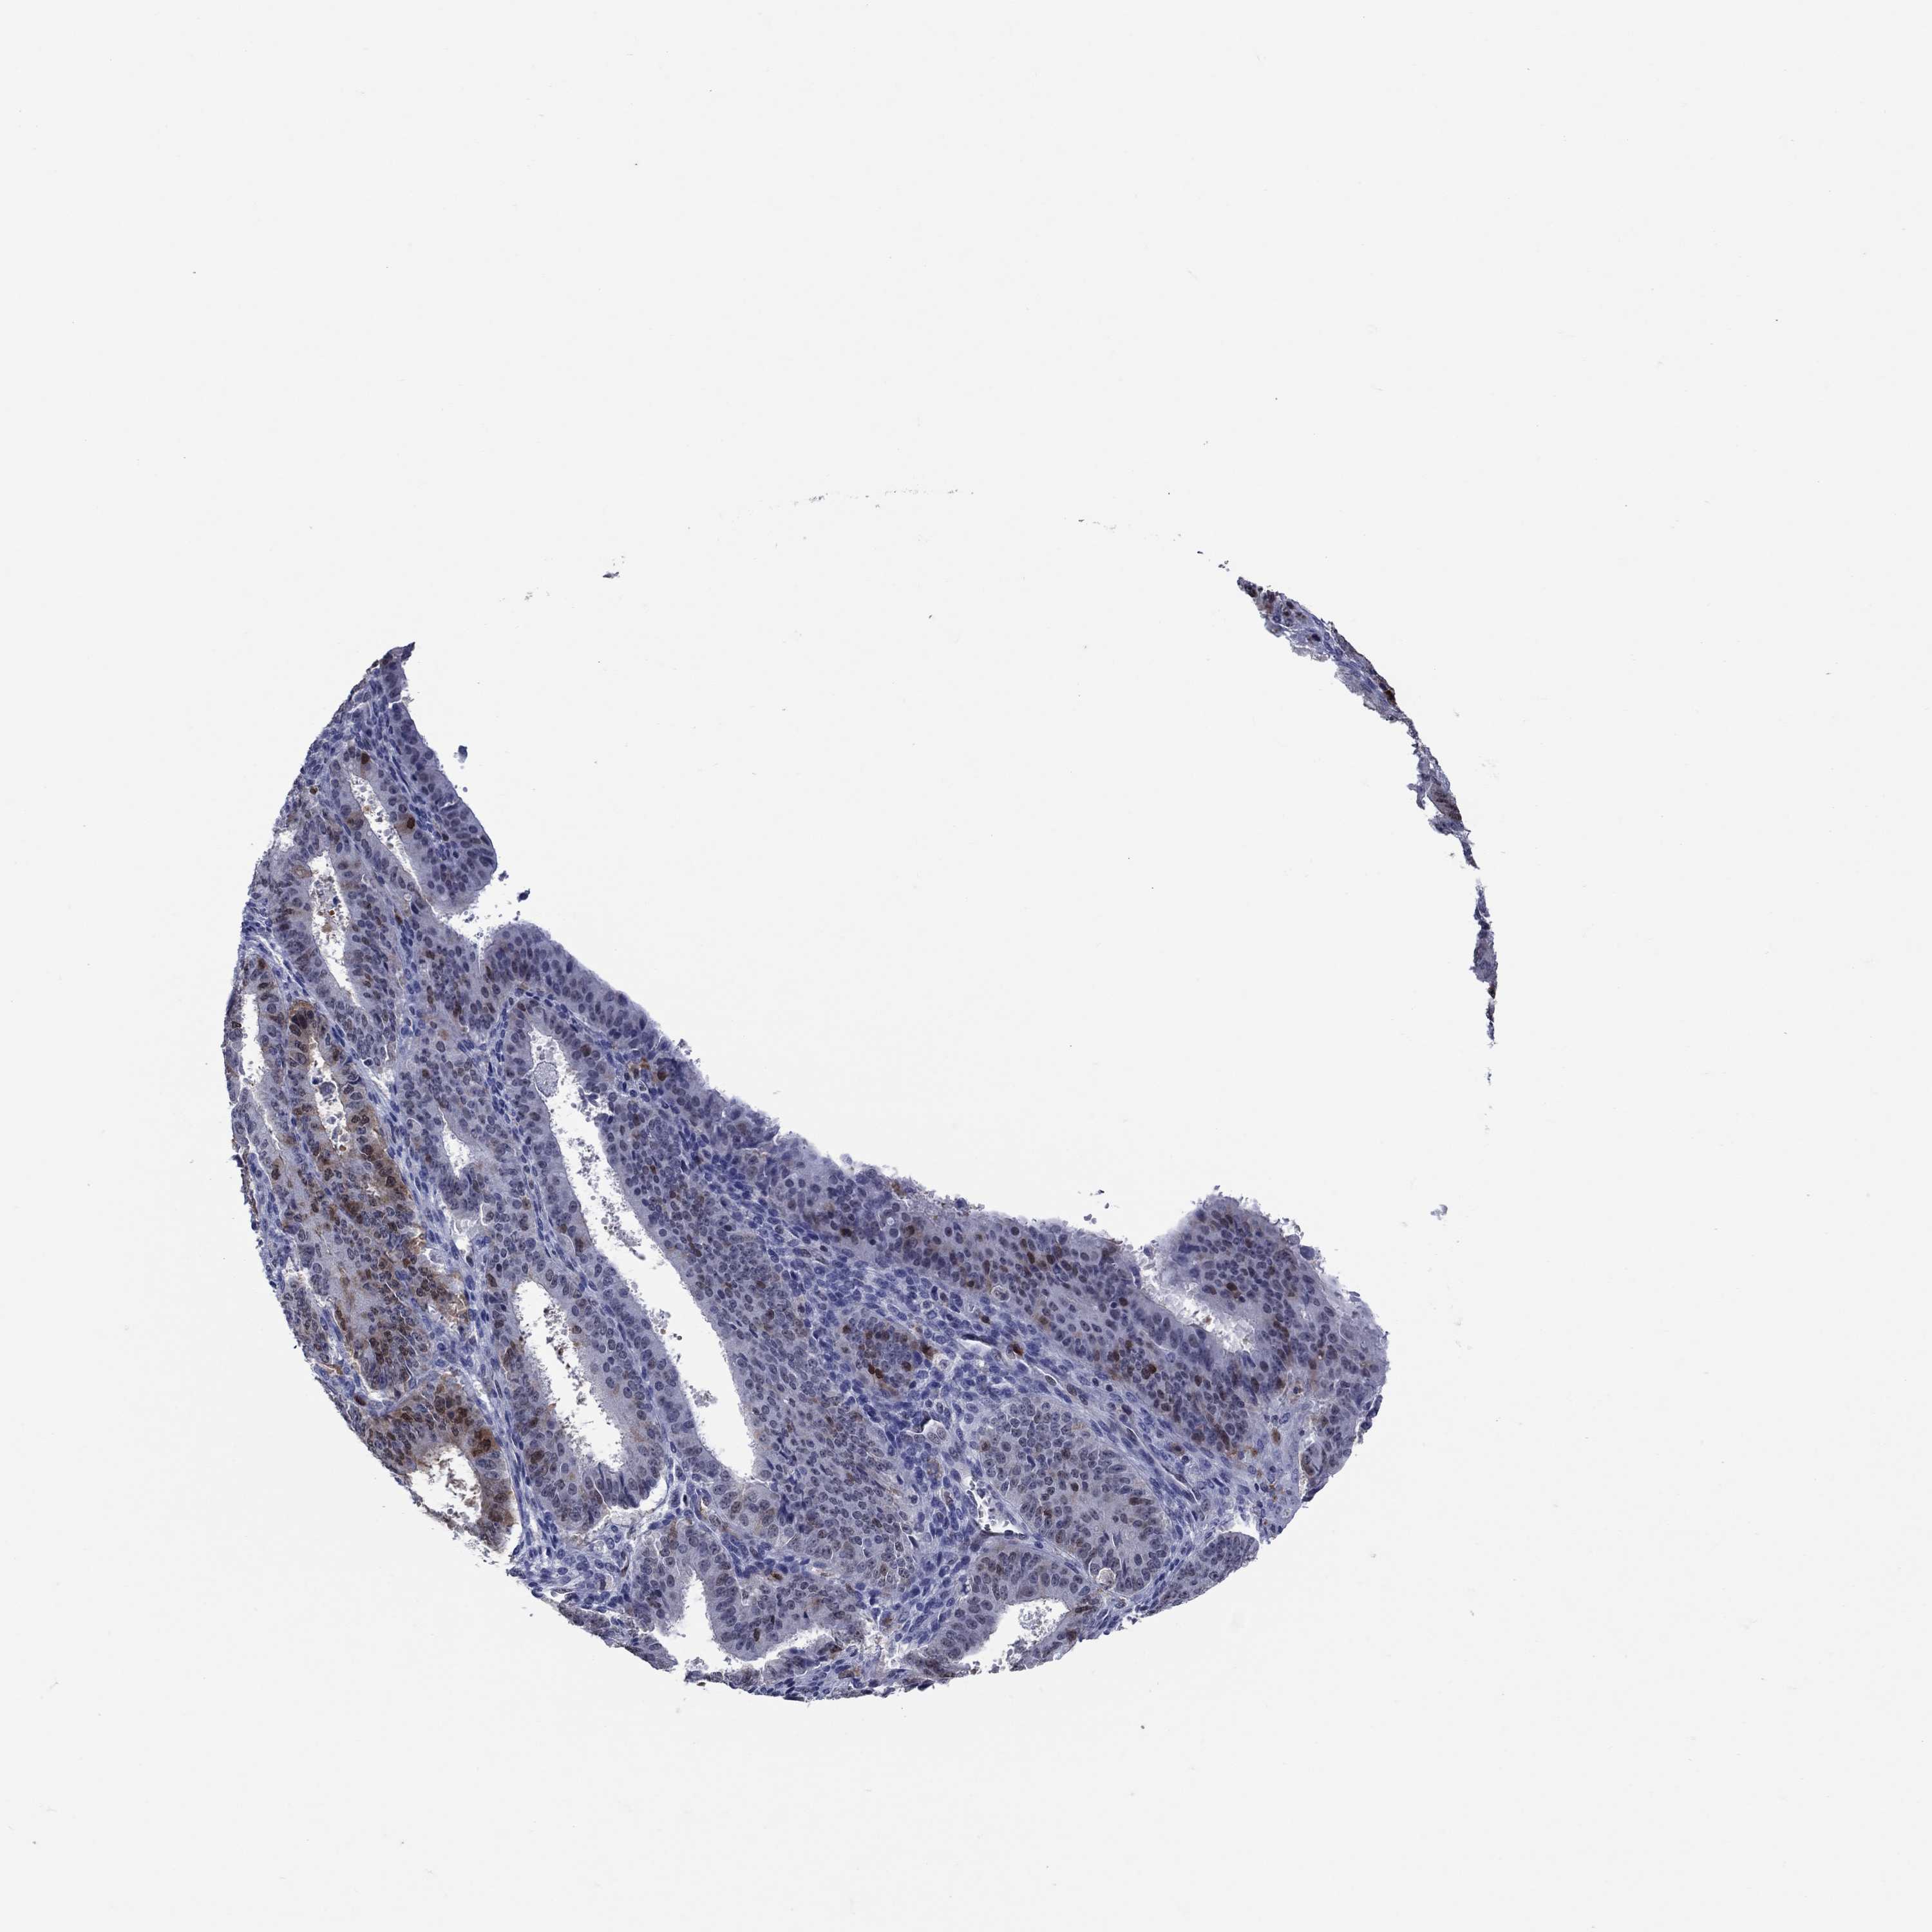

OVARIAN CANCER - Protein expressioni

A mouse-over function shows sample information and annotation data. Click on an image to view it in a full screen mode. Samples can be filtered based on level of antibody staining by selecting one or several of the following categories: high, medium, low and not detected. The assay and annotation is described here.

Note that samples used for immunohistochemistry by the Human Protein Atlas do not correspond to samples in the TCGA dataset.

Antibody stainingi

Antibody staining in the annotated cell types in the current human tissue is reported as not detected, low, medium, or high, based on conventional immunohistochemistry profiling in selected tissues. This score is based on the combination of the staining intensity and fraction of stained cells.

Each image is clickable and will lead to virtual microscopy that enables deeper exploration of all samples and also displays staining intensity scores, fraction scores and subcellular localization as well as patient and tissue information for each sample.

Antibody HPA074922

Antibody CAB002784

Carcinoma, endometroid